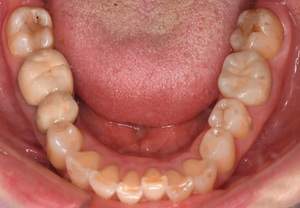

症例写真(治療後)

治療後:

矯正治療と虫歯の治療すべて終わったときの写真になります。見た目も最初の頃とは全く違いますし、お口の中もすごく綺麗です。